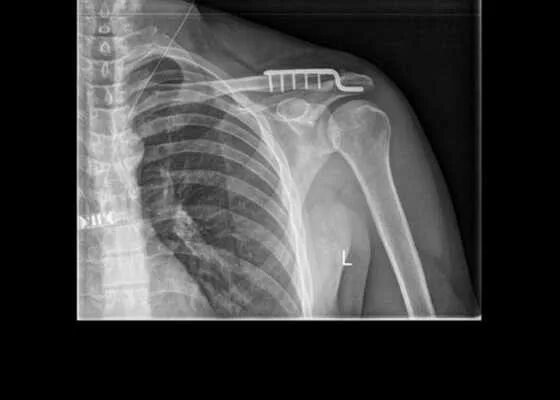

Вывих акромиально ключичного сочленения